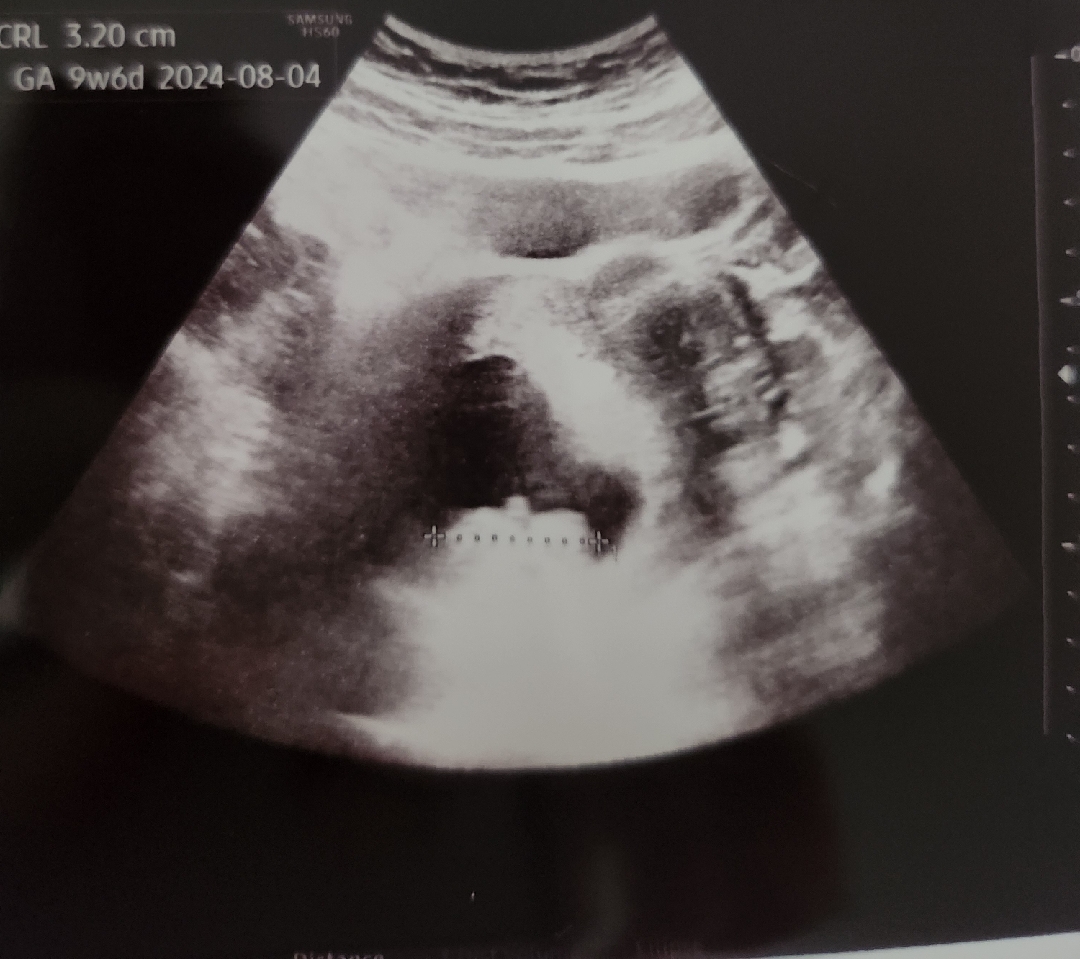

10주 1일에 초음파 찍었는데 귀여운 젤리곰 본다는 생각에 들떠서 갔는데 배초음파로 본다길래 1차 읭 싶다가 결국 이렇게 밖에 안보여서 속상했어요..🥲다른분들 보면 굉장히 크고 선명하게 보이던데 기계의 문젠지 제가 뱃샬이 많아서 그런건지 😅..이유를 아시는분 있나요?뱃샬때문이면 앞으로 이렇게 흐릿하게 애기를 만나야하나...ㅋㅋㅋ

저건 선생님이 초음파각도를못맞춘듯해요 배살하고는 연관있겟지만 저정도는아니에요~

병원 초음파 기계 문제 아닐까요? 저 배촘파 9주에 봤을때도 잘보였거든요 올려주신 사진은 아예 안보이는거같아서.. 또 사진이라면 의사쌤이 아무렇게나 각도 안잡구 막 찍어주신건 혹시 아닐까 하는 의심이 드네요;;